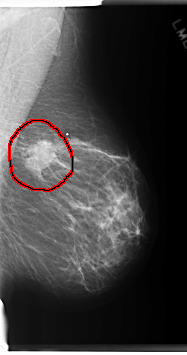

C_0220_1.LEFT_MLO

LEFT_MLO LINES 6032 PIXELS_PER_LINE 3176 BITS_PER_PIXEL 12 RESOLUTION 50 OVERLAY

FILE: C_0220_1.LEFT_MLO.OVERLAY

TOTAL_ABNORMALITIES 1

ABNORMALITY 1

LESION_TYPE CALCIFICATION TYPE AMORPHOUS DISTRIBUTION CLUSTERED

LESION_TYPE MASS SHAPE IRREGULAR MARGINS MICROLOBULATED

ASSESSMENT 5

SUBTLETY 5

PATHOLOGY MALIGNANT

TOTAL_OUTLINES 1

BOUNDARY